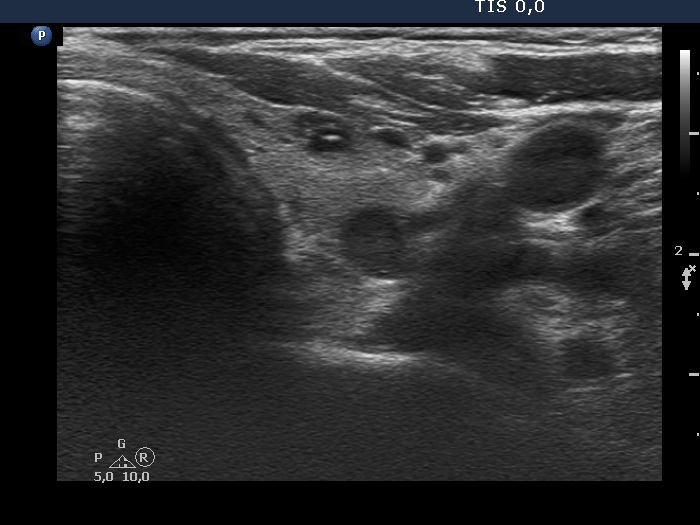

Halo sign and vascular pattern of nodules - case 2248 (ultrasonographic picture 5)

Lower part of the left lobe, another transverse scan. The echogenic line in the ventral lesion is caused by posterior enhancement.